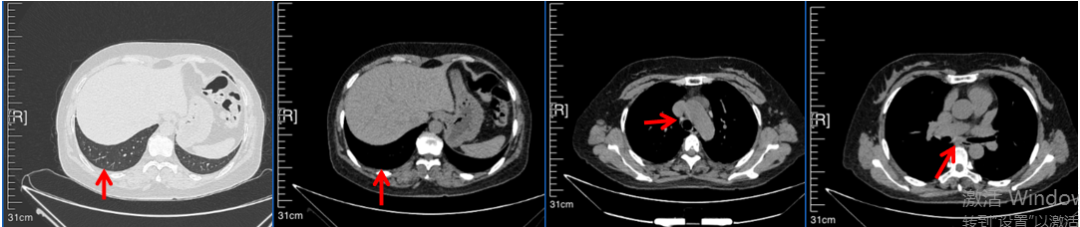

2016年1月复查CT提示支气管截断可见新发小结节,一线治疗采用培美曲塞+DDP方案化疗4周期(培美曲塞3.36,DDP 480mg)。化疗后复查胸部CT:右肺见不规则结节样影,最大层面大小约19mm*8mm,较前比较明显增大,疗效评估PD。2017.3-2017.4予单药多西他赛化疗3周期,疗效评估SD。2018年5月末复查CT提示结节较前增大,评效为PD,2018年6-10月予多西他赛+CBP化疗4周期,疗效评估SD。2022年5月患者出现活动后气短,复查胸部CT示右肺膨胀不良;右侧胸腔积液增多。胸腔积液包埋病理示符合肺腺癌细胞。行NGS基因检测:EML4:exon13-ALK:exon20融合。PD-L1(克隆号22C3)TPS<1%。

诊疗经过:2022年5月始口服克唑替尼3个月,出现肝功能异常(DILI 2级伴临床症状),改用恩沙替尼靶向治疗至今,目前评效为维持PR。恩沙替尼应用期间出现轻度肝功能异常(DILI 1级),对症处理后好转。截止目前PFS 33个月。

2018.07

2022.05

2022.08

2023.05

2024.12